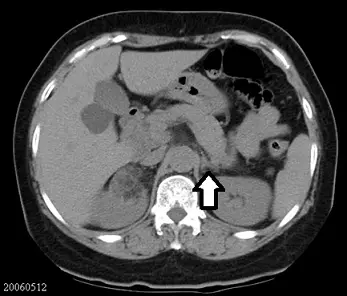

一張腹部CT影像如下圖,箭號所指構造為何?

此為一張腹部橫切面 CT 影像。圖中右側可見肝臟,左側可見脾臟,中後方為脊椎體,腹主動脈與下腔靜脈位於脊椎前方。雙側腎臟的上半球(upper pole)亦在視野中。白色箭號所指為一個位於左腎上極前內側、左側橫膈腳外側的軟組織構造,其外觀呈現特徵性的倒 V 形或 Y 字形。

- D. 左腎上腺(left adrenal gland):解剖位置正好位於左腎上極的前內側、胰臟尾部後方以及左側橫膈腳外側,且在 CT 上呈現典型的倒 V、Y 或線形外觀,與影像中箭號所指完全吻合。

根據影像顯示,箭號標示的構造在解剖學上明確位於左側腎臟上極的前內側。透過其特有的解剖相對位置以及呈現出